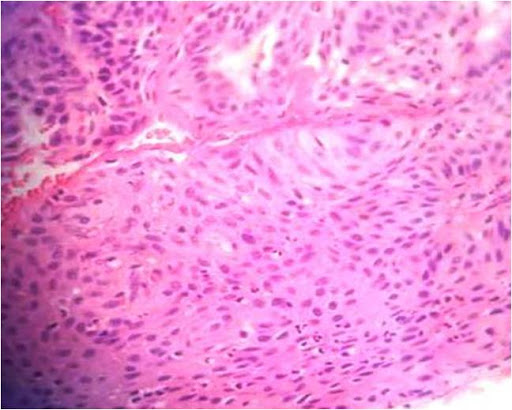

Basal cell carcinoma is the most common adnexal tumor; however its occurrence in the oral cavity is rare and controversial.[7],[8],[9],[10] Clinically, they present as non-healing ulcers. Histopathologically, they exhibit numerous tumor islands composed of basaloid cells in the lamina propria. (Figure 1) Tumor islands exhibit a prominent palisading of peripheral basal cells (Figure 2). The diagnosis of IOBCC solely on histopathological grounds, however, is not easy, due to their histological resemblance with peripheral ameloblastoma (PA).[11],[12] The differentiation between IOBCC and PA is of utmost importance since the former is malignant.

Figure 1. Tumor islands of basal celss in lamina propria (Hematoxylin and eosin stain x20).

Figure 2. Tumor islands exhibit peripheral palisading (Hematoxylin and eosin stain x40).